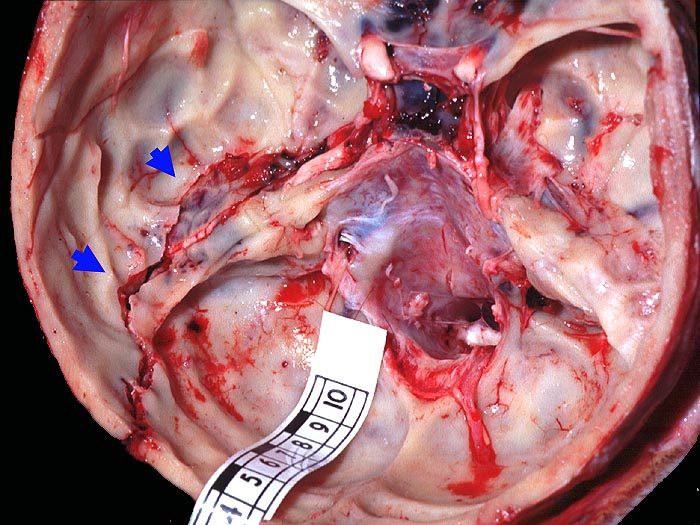

Frische Schädelbasisfraktur im Bereich der vorderen Schädelgrube entlang dem Os ethmoidale, im Bereich der Pars petrosa des Os temporale sowie bis in den Bereich der hinteren Schädelgrube entlang der Sutura lambdoidea links reichend.

Frische kortiko-subkortikale Hirnkontusionen. Blutige Otorrhoe links. Herdförmige diffuse frische Subduralblutungen (ohne raumfordernde Wirkung). Monokelhämatom.